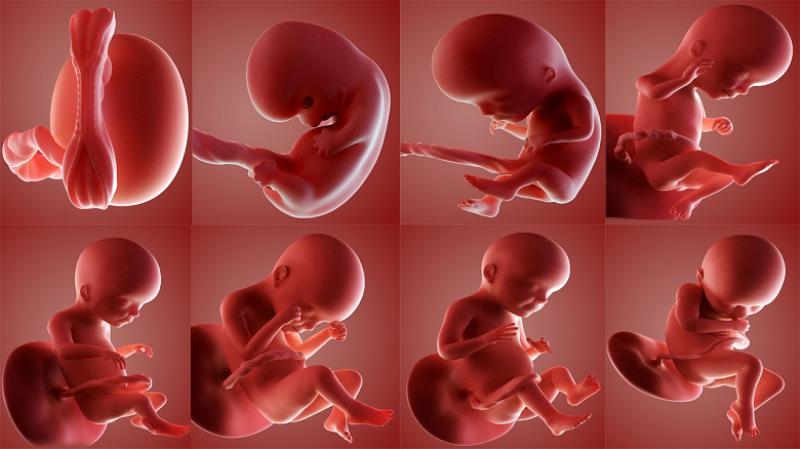

10 haftalık gebelik, hamileliğin ikinci trimesterine geçişin başlangıcını işaret eden önemli bir dönemdir. Bu dönemde, fetüs hızla gelişmekte ve anne vücudunda çeşitli değişiklikler meydana gelmektedir. Bu makalede, 10 haftalık gebeliğin fiziksel ve psikolojik etkileri, fetal gelişim, beslenme önerileri ve dikkat edilmesi gereken noktalar üzerinde durulacaktır. Fetal Gelişim 10. hafta itibarıyla fetüs, yaklaşık 3,5 cm uzunluğundadır ve bu haftada önemli gelişim aşamalarından geçmektedir. Aşağıda fetüsün bu aşamadaki gelişimsel özellikleri sıralanmıştır: